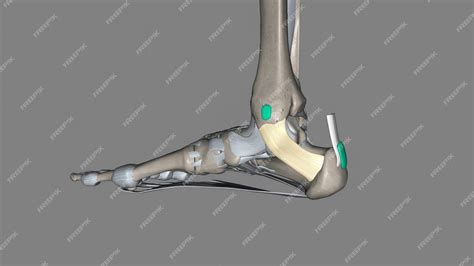

Anatomical view of the ankle and foot structure

The flexor retinaculum is a thick, fibrous band that stretches from the medial malleolus—the bony prominence on the inside of your ankle—to the medial tubercle of the calcaneus, or heel bone. Its primary purpose is to act as a ligamentous sheath, binding down the tendons of the deep muscles of the posterior compartment of the leg.

By holding these tendons close to the ankle bone, the flexor retinaculum foot structure prevents "bowstringing" during movement. When the muscles in your calf contract to point your toes downward or flex your foot, these tendons would naturally pull away from the bone if not for the restraining force of the retinaculum. This allows for efficient transfer of force, enabling smooth walking, running, and jumping.